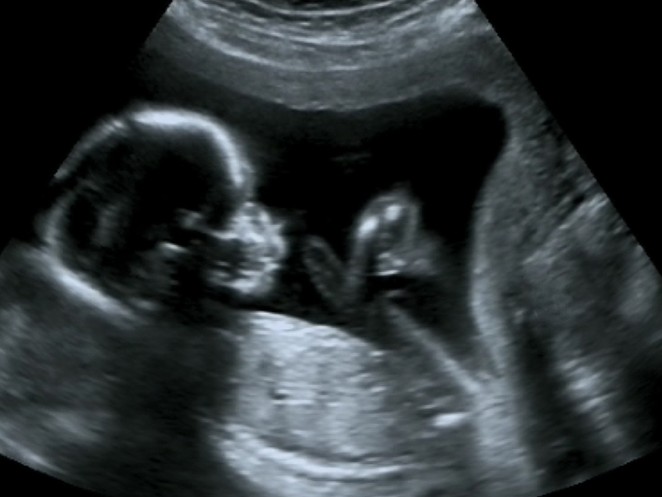

Mädchen oder Bub? Eltern dürfen es erst nach der 12. Woche der Schwangerschaft erfahren